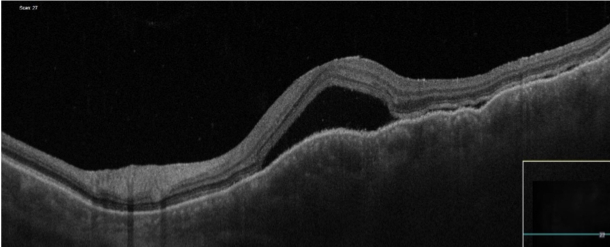

OCT

急性期原田病におけるOCT所見。隔壁を伴った漿液性剝離、脈絡膜肥厚が観察できる。

出典

img

1: 著者提供